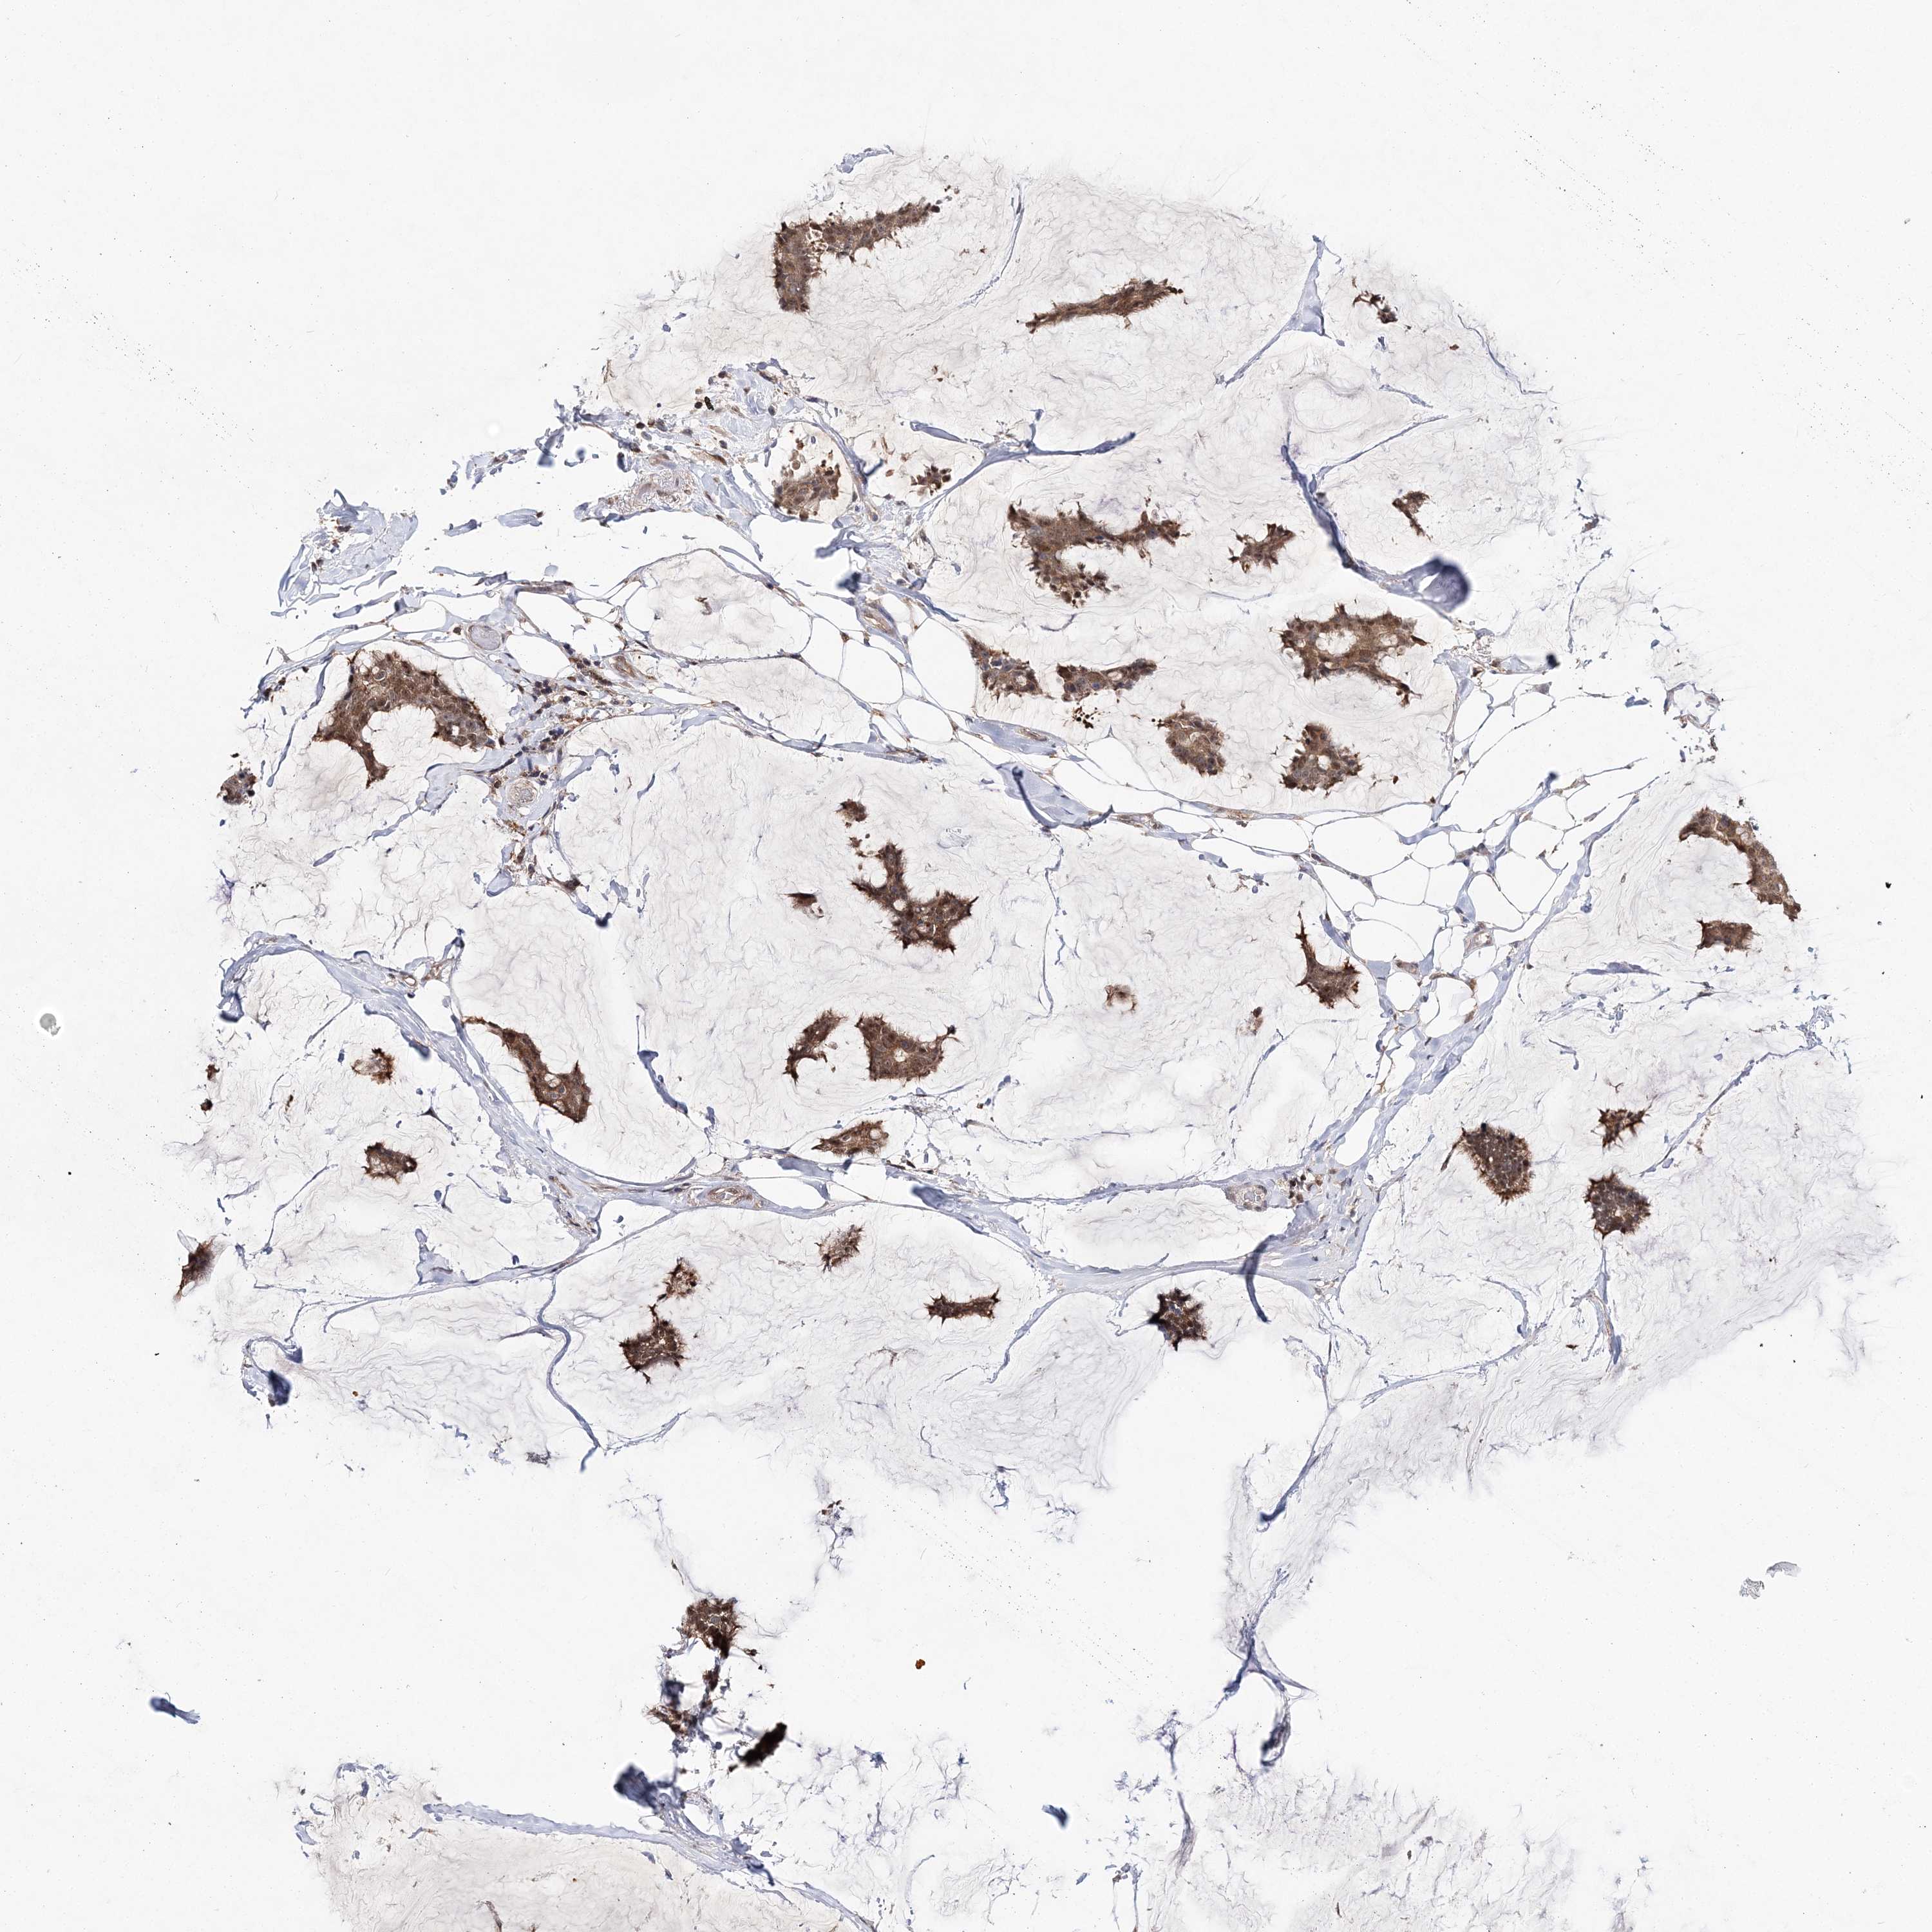

CANCER BREAST CANCER Show tissue menu

BRCA TCGA BRCA VALIDATION PROTEIN EXPRESSION

Breast cancer

Human cancer